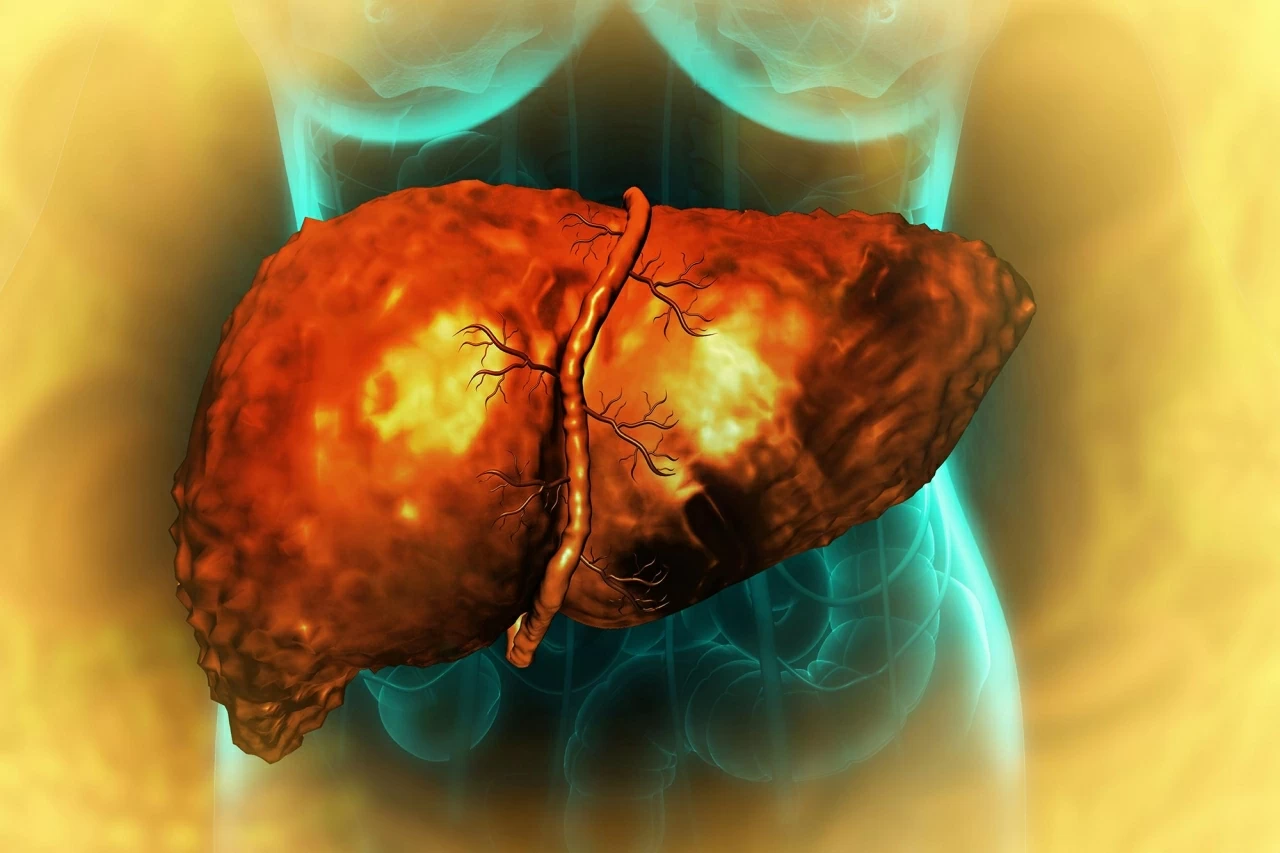

Chế độ ăn nhiều chất béo làm tăng nguy cơ ung thư gan

Chế độ ăn nhiều chất béo có thể lập trình lại tế bào gan, buộc chúng chuyển sang trạng thái sinh tồn giống tế bào gốc, qua đó làm tăng nguy cơ ung thư gan. (Nguồn: Shutterstock)

Nghiên cứu mới của Viện Công nghệ Massachusetts (MIT), công bố trên tạp chí Cell, cho thấy chế độ ăn nhiều chất béo không chỉ gây tổn thương gan mà còn làm biến đổi sâu sắc cấu trúc và chức năng tế bào gan, tạo điều kiện cho ung thư phát triển.

Theo nhóm nghiên cứu, khi tiếp xúc kéo dài với lượng chất béo dư thừa, các tế bào gan trưởng thành mất dần trạng thái chuyên biệt, quay về dạng nguyên thủy giống tế bào gốc. Sự thích nghi này giúp tế bào tồn tại trước căng thẳng chuyển hóa, nhưng đồng thời làm tăng nguy cơ biến đổi ác tính.

Thí nghiệm trên chuột ăn chế độ giàu chất béo, kết hợp giải trình tự RNA đơn bào, cho thấy các gien thúc đẩy sống sót và phân chia được kích hoạt mạnh, trong khi các gien đảm nhiệm chức năng gan bình thường dần bị ức chế. Kết quả, hầu hết chuột đều phát triển ung thư gan vào cuối thí nghiệm.

Phân tích mô gan của bệnh nhân ở nhiều giai đoạn bệnh cho thấy kết quả trên người phù hợp với thí nghiệm ở chuột. Theo thời gian, các gien duy trì chức năng gan suy giảm, trong khi các gien liên quan đến trạng thái tế bào chưa trưởng thành hoạt động mạnh hơn và dễ bị hủy hoại sau khi ung thư xuất hiện.